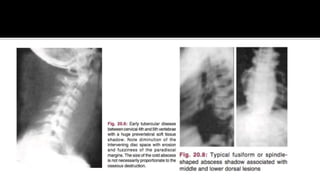

 AP :

▪ NARROWING DISC SPACE

▪ FUSIFORM SHADOW

(PARAVERT ABSCESS)

 LATERAL :

▪ KYPHOTIC DEFORMITY

▪ LOSS BODY HEIGHTVERT

BODY

▪ END PLATE IRREGULAR

 Produced by extension ofTB granulation tissue and collection

of abscess in the paravertebral region

 Abscess in the cervical region usually presents as a soft tissue

shadow between the vertebral bodies and pharynx and

trachea. Normal value: above cricoid cartilage (C6): 0,5 cm;

below 1,5 cm

 In the upper thoracic abscess, on AP view cast aV-shaped

shadow stripping the lung apices laterally and downwards.

 Abscess below the levelTh4 vertebra produce typical fusiform

shape